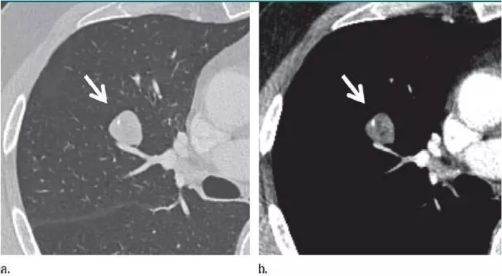

在中国人的印象里 心和肺一直是“形影不离”的 海尔兄弟 成语里有 撕心裂肺 狼心狗肺 没心没肺 …… 医学术语里有 心肺功能 心肺复苏 心肺康复 …… 尤其是当肺部查出“小阴影” 心更是脱不了关系 每天都惴惴不安 今天肿医君就来带大家看看 这让人烦恼的 肺部结节 Part.1: 肺部结节 真实病例: 张阿姨今年48岁,单位体检结果显示,肺上有一个0.8cm的小结节。张阿姨听说肺结节会变成肺癌,她担心极了,让儿子帮忙上网查询,向其他人咨询,可她得到的建议多种多样,让刘阿姨无所适从。 慢慢长大会不会变成肺癌啊 肺癌是世界上发病率及死亡率最高的恶性肿瘤,也是我国发病率和死亡率最高的疾病。目前约 75% 的肺癌患者在诊断时已属晚期,5年生存率仅为 15.6%。提高肺癌生存率的唯一途径是端口前移,早发现、早诊断和早治疗。 美国《化学文摘》2018全球癌症统计报告显示 肺癌(蓝色)高居发病率和死亡率之首 全球发病率11.6% 全球死亡率18.4% 湖南省肿瘤医院胸外一科 主任医师 陈跃军 很多患者忧心忡忡,不知道是否该进行进一步检查。如果对体检报告中的一些疾病迹象置若罔闻,等“小结节”长大变成了“肿块”,往往已错过最佳手术时机。那么我们应该怎么正确对待肺部结节呢? Part.2: 结节的分类 知识点 肺部结节(solitary pulmonary nodule,简称SPN)是肺实质完全包围的单发小病灶,类圆形或不规则形状,通常边界清晰,由肺实质包裹,不累及肺门和胸腔纵隔胸膜,不引发肺炎、肺不张或胸腔积液的组织。 肺结节分类如下 按大小: 肺结节中,直径1cm以内的称为小结节,直径0.5cm以内为微结节。局部病灶直径>3cm者称为肺肿块,也有医院将其报告为肺肿物或肺占位。 肺部结节尺寸越大,肺癌的可能性相对较大。 按数量: 肺结节可以是孤立性或多发性,孤立性肺结节即单个病灶,多无明显症状,属于边界清楚、密度增高且周围被含气肺组织包绕的软组织影。2个及以上病灶称为多发性肺结节。 肺结节的个数与肺癌可能性没有相关性 按密度: 根据病灶密度不同,肺结节还可分为实性肺结节和亚实性(非实性)肺结节,后者包括纯磨玻璃样结节。实性肺结节是肺内局限的密度增高影,病变密度相对较高,掩盖其中走行的肺细小支气管影和血管影(肺纹理);纯磨玻璃结节指CT显示的肺内密度稍增高影,通过病灶仍然能看到肺纹理影,就像透过磨玻璃观察到相对模糊的影像一样。 磨玻璃样结节尤其是持续存在的磨玻璃样结节,一般是肿瘤性病变 湖南省肿瘤医院胸外一科 主任医师 陈跃军 发现肺结节之后,不用过分紧张,但也不能掉以轻心,大部分肺结节都是良性的,只有少数肺结节是恶性的。 Part.3: 区分结节性质 结节良性的三大表现 1、 结构清晰,边缘平滑。内含脂肪和钙化的实性结节(箭头),符合错构瘤表现。建议进一步 CT 随访。 源自美国Fleischner 学会2017 年公布案例图(下同) 2、 有明显钙化痕迹。CT 图像显示边界清楚的中心钙化(a)或层状钙化(b)结节,均为典型的肉芽肿表现。建议进一步 CT 随访。 3、没有变大的趋势,甚至逐渐消失。(a)左肺上叶层厚 1 mm 的 CT 横断面图像,显示一个模糊的 10 mm 大小磨玻璃样结节(箭头)。(b)4 个月后的 CT 随访图像,显示未经治疗的病变在随访间期消失,符合良性病因,如局灶性感染。 结节恶性的三大表现 1、 毛刺状结节 左肺上叶层厚 1 mm 的 CT 横断面图像,显示一个可疑的实性毛刺状结节(箭头)。手术证实为浸润性腺癌。 2、 磨玻璃区域逐渐长大的结节 (a)右肺中部层厚 1 mm 的 CT 横断面图像,显示一个 10 mm 大小的纯磨玻璃样结节(箭头)。(b)同一位置 15 个月后的 CT 随访图像,显示病变的不透明度只有很小增加。(c)取得 b 图 10 个月后,同一位置的 CT 图像,显示结节已发展成较大的实性结节。手术切除证实为 1A 期浸润性鳞屑样为主的腺癌 3、实性结节逐渐变大的结节 (a)右肺下叶上段层厚 1 mm 的 CT 横断面图像,显示一个高度可疑(较大、磨玻璃样外观和实性形态)的部分实性结节(箭头)。(b)3 个月后的 CT 随访图像显示,实性成分的大小逐渐增加。手术显示为浸润性腺癌。 除了上述影像资料,咨询者的生活方式也是判断依据。 肺癌的高危人群 (1)年龄在55岁以上; (2)年数乘以每天吸烟的支数>400支*年的吸烟患者,其中也包括曾经吸烟,但戒烟时间不足15年者;被动吸烟者; (3)有职业暴露史(石棉、铍、铀、氡等接触者); (4)有恶性肿瘤病史或肺癌家族史; (5)有慢性阻塞性肺疾病(COPD)或弥漫性肺纤维化病史。 Part.4: 发现结节怎么做? 1、肺部小结节并不等于肺癌,并且大部分是良性的,有的通过保守治疗如抗炎或抗痨治疗,甚至不做任何治疗观察后消失。因为人体有自身免疫力的,只要营养好,一般的炎性病变可自行吸收。 2、当医生判断结节恶性可能性较小时,还是建议患者要定期检查胸部CT。5毫米以下的微结节每年复查一次,5至10毫米的小结节每三个月复查一次,随访三至五年。 CT在肺内病变中的诊断优势非常明显,CT通过显示组织横断面及三维结构图像进行诊查,有效避免了肺与心脏、纵隔、横膈等组织的重叠,能发现肺尖、脊柱旁、靠近胸膜、心脏后方等部位胸片难以发现的病灶。另外,低剂量CT筛查所产生的射线剂量很低,对人体的影响极低。 3、当医生判断为恶性可能性较大时,应早期进行手术(胸腔镜)治疗。国内外多个研究结果显示,经过手术治疗的I期患者的10年生存率达到了90%以上。 目前微创胸腔镜手术是治疗肺部小结节、早期肺癌的主要方法。胸腔镜手术应用广泛,只需一个1cm胸腔镜观察孔和一个2-3cm操作孔,行肺叶或肺段切除术,疗效明确,创伤非常小,疼痛轻,术后恢复快,不需要做任何的化疗和放疗。 在我们临床工作中对上千例磨玻璃结节、微小结节患者的长期临床观察研究结果显示,90%以上患者的结节没有发生变化,10%的患者在随访过程中发现结节长大或实质成分增加等改变,及时手术,但没有一例出现复发转移,所以只要找对了专家,定期随访,并不会耽误治疗。 最危险的情况其实是病人发现肺部结节去看医生,医生考虑肺部小结节可暂时不处理,建议定期复查,而病人把不手术、不服药误认为没病,一直拖到出现症状后再去就诊,耽误了病情。